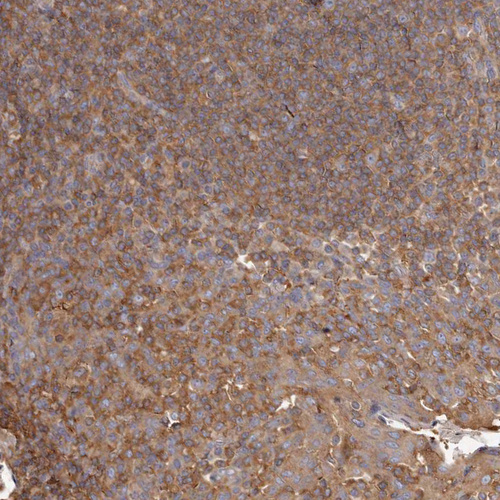

Immunohistochemical staining of human tonsil shows moderate cytoplasmic/ membranous positivity in non-germinal center cells.